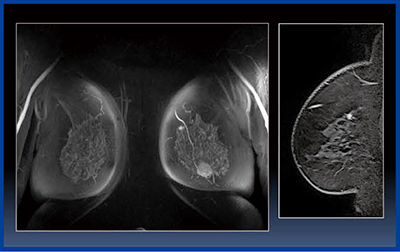

図1に,触知で発見され,MRIガイド下生検を行った乳がんの術前MRIを示す。頭側方向の乳房の別の区域に5mm程度の不整形の腫瘍が認められ,MRIガイド下生検を行ったところ,同側乳房に2つの乳がんが検出されたため,乳房温存手術を断念して全摘手術を実施した。

図1 MRIでしか見えない乳がん

触知で発見され,MRIガイド下生検を行った乳がんの術前MRI